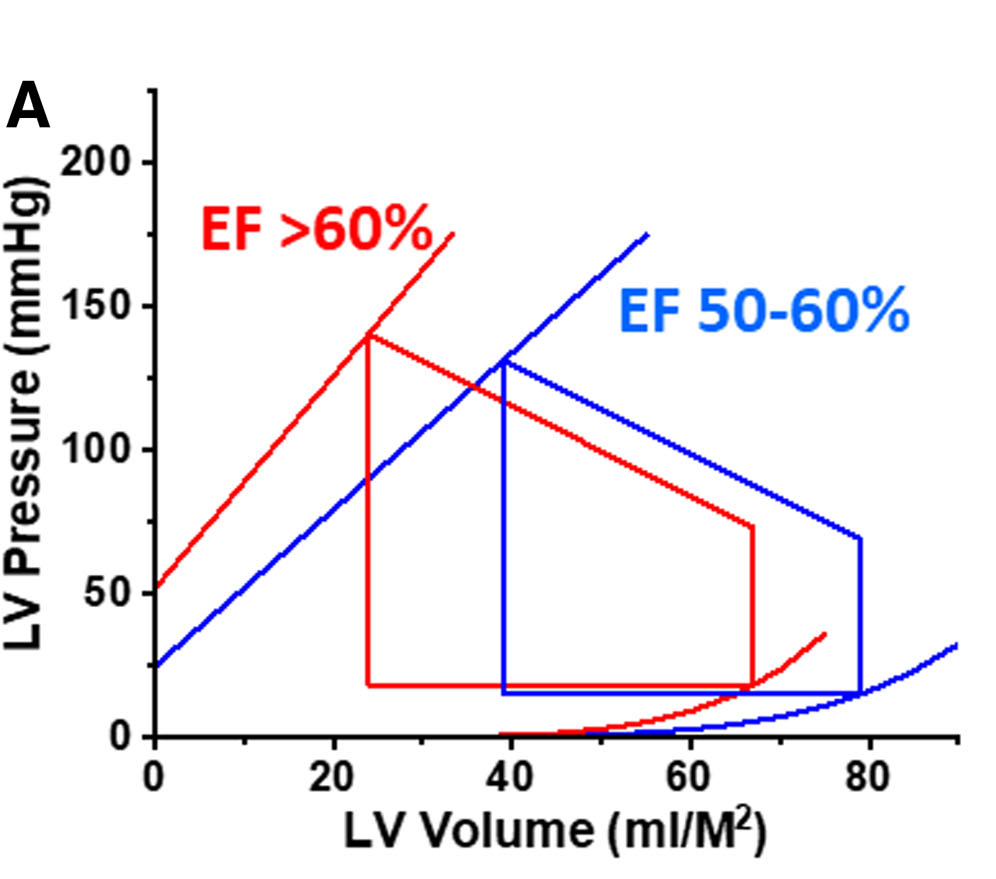

- Ejektionsfraktion

- prozentuelle Anteil des enddiastolisches Volumen, der in die Aorta ausgeworfen wird

Unterteilung Herzinsuffizienz

- LV-EF ≤40%

Herzversagen mit eingeschränkter Ejektionsfraktion

Heart Failure with reduced Ejection Fraction, HFrEF - LV-EF ≥50%:

Herzversagen mit erhaltener Ejektionsfraktion

Heart Failure with preserved Ejection Fraction, HFpEF - LV-EF ≥40-50%:

Herzversagen mit leicht eingeschränkter Ejektionsfraktion

Heart Failure with mild reduced Ejection Fraction, HFmrEF

- Mortalität steigt auch bei Abweichungen der LV-EF >60% an (n = 203 135)

- unabhängig von Alter, Geschlecht oder anderen relevanten Begleiterkrankungen

- = Herzinsuffizienz mit supranormaler Ejektionsfraktion, HfsnEF

... weitere Fakten

Herzinsuffizienzen mit LVEF >60% besitzen im Gegensatz zu solchen von 50-60%

- kleineres endsystolisches und enddiastolisches linksventrikuläres Volumen (ESV, EDV)

- höheren enddiastolischen LV-Druck

- steilere, nach links verschobene endsystolische und enddiastolische Druck-Volumen-Beziehung (EDPVR)

- reagiert empfindlicher auf Verringerung der Vorlast

- mit stärkerer Verringerung von Blutdruck und Schlagvolumen